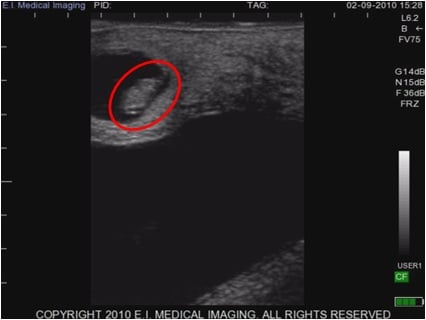

What is the red circle pointing to?

Pregnancy from ultrasound (cow)